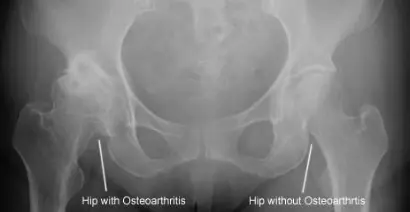

2. Osteoarthritis (OA)

- A weaker indication for steroid injection